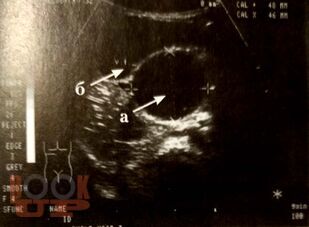

Учебное пособие содержит материал, отражающий современные данные о лечебно-диагностических концепциях основных аномалий развития и приобретённых хирургических заболеваниях детского возраста. В пособии раскрыты ключевые позиции, этиологии, патогенеза, классификации, клинических проявлений, диагностики, консервативного и хирургического лечения, возможных осложнений и исходов хирургических заболеваний у детей. Сделан акцент на эмбриопатогенез и пренатальную диагностику врождённых аномалий развития у детей. Пособие содержит перечень вопросов для самоконтроля, тестовые задания и ситуационные задачи.